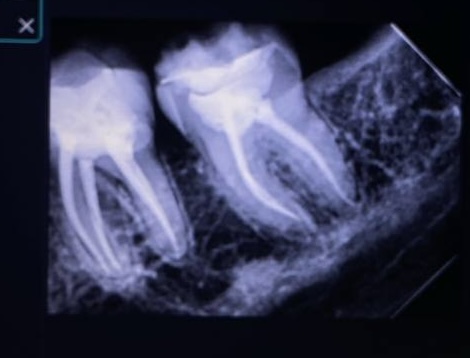

Before fishing the walls

After finishing and sandblasting

Ever x to replace the dentin

Overlay prep retention men distally